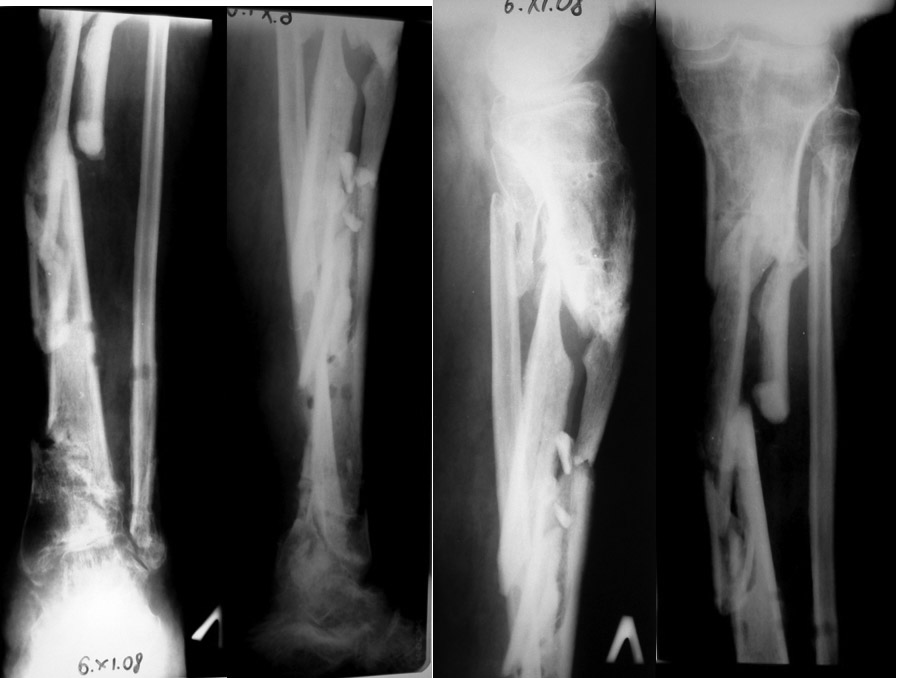

Больной К 45 лет,

ДЗ: ложный сустав левой голени.

Травма 1 год назад, ТСТ. открытый фрагментарный перелом левой голени, перелом мыщелков левой голени, н.з малоберцовой кости. +плечо, Алкогольный делирий.

В настоящий момент левая нижняя конечность не опорная, имеется патологическая подвижность в с.з голени. Раны зажили более 6 мес назад.

Обдумываем варианты лечения: Аппарат Илизарова: два кольца на проксимальный отдел голени, два кольца на промежуточный фрагмент, два кольца на дистальный, остеотомия малоберцовой кости. 1.Закрыто сделать дистракцию-компрессию между отломками проксимального и дистального фрагментов 2. Или открыто резекция концов фрагментов с укорочением. 3 Удалить целиком средний фрагмент и <зарастить> регенератом.